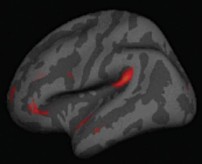

Acima: Regiões corticais mais espessas em pessoas que meditam aparecem em ambos os hemisférios cerebrais. Este mapa estatístico ilustra esta intensidade em cada ponto da superfície cortical.